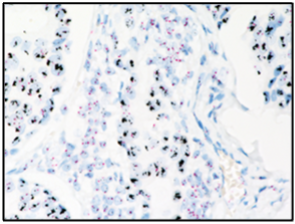

罗氏诊断此次全新推出的HER2/17号染色体DNA双探针(原位杂交法),通过二硝基苯(DNP)标记的探针检测HER2,用地高辛(DIG)标记探针检测17号染色体着丝粒(CEP17),双探针设计用于检测 HER2基因相对于17号染色体的比率来评估HER2基因扩增状态,可缩短检测时间,有效助力临床更快地制定治疗决策,优化乳腺癌患者的精准诊疗。

使用VENTANA HER2 Dual ISH DNA Probe Cocktail检测法检测HER2基因扩增状态

据悉,该检测可在罗氏诊断BenchMark ULTRA全自动免疫组化染色系统上实现全自动化运行,有效确保检测的质量和效率。在结果判读上,仅使用普通光学显微镜就能随时、精准观察组织形态和信号状态,此外,染色切片还可长期保存,便于结果查阅、复审及疑难病例讨论 ,全面满足病理实验室规范化、标准化检测的需求。